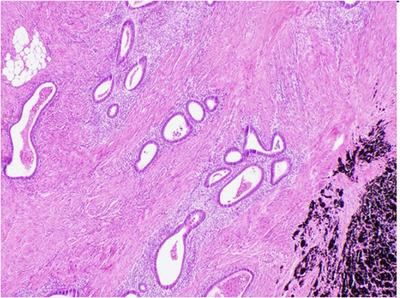

Despite endometriosis being a relatively common chronic gynecological condition in women of childbearing age, small bowel endometriosis is rare. Presentations can vary from completely asymptomatic to reported symptoms of abdominal pain, bloating, and diarrhea. The following two cases depict very atypical manifestations of ileal endometriosis that presented as obscure intermittent gastrointestinal bleeding and bowel obstruction requiring surgical intervention. The first case describes a previously healthy 40-year-old woman with severe symptomatic iron deficiency anemia and intermittent melena. A small bowel enteroscopy diagnosed multiple ulcerated strictures in the distal small bowel as the likely culprit. Despite nonsteroidal anti-inflammatory drug-induced enteropathy being initially considered as the likely etiology, histopathological examination of the resected distal ileal segment revealed evidence of endometriosis. The second case describes a 66-year-old with a presumptive diagnosis of Crohn's disease who reported a 10-year history of intermittent perimenstrual abdominal pain, diarrhea, and nausea with vomiting. Following two subsequent episodes of acute bowel obstruction and surgical resection of the patient's stricturing terminal ileal disease, histopathological examination demonstrated active chronic inflammation with endometriosis. Small bowel endometriosis should be considered as an unusual differential diagnosis in women who may present with obscure gastrointestinal bleeding from the small bowel or recurrent bowel obstruction.

尽管子宫内膜异位症是育龄期女性相对常见的慢性妇科疾病,但小肠子宫内膜异位症却很罕见。其表现形式多样,从完全无症状到出现腹痛、腹胀和腹泻等症状。以下两个病例描述了回肠子宫内膜异位症非常不典型的表现,分别为不明原因的间歇性胃肠道出血和肠梗阻,均需要手术干预。第一个病例是一名40岁的既往健康女性,患有严重的症状性缺铁性贫血和间歇性黑便。小肠肠镜检查诊断为远端小肠多发溃疡狭窄,这可能是病因所在。尽管最初认为非甾体抗炎药引起的肠病是可能的病因,但对切除的远端回肠段进行组织病理学检查发现了子宫内膜异位症的证据。第二个病例是一名66岁的女性,初步诊断为克罗恩病,她有10年的间歇性经前期腹痛、腹泻、恶心伴呕吐病史。在随后两次急性肠梗阻发作以及对患者狭窄的末端回肠疾病进行手术切除后,组织病理学检查显示为伴有子宫内膜异位症的活动性慢性炎症。对于可能出现不明原因的小肠胃肠道出血或反复肠梗阻的女性,小肠子宫内膜异位症应被视为一种不常见的鉴别诊断。